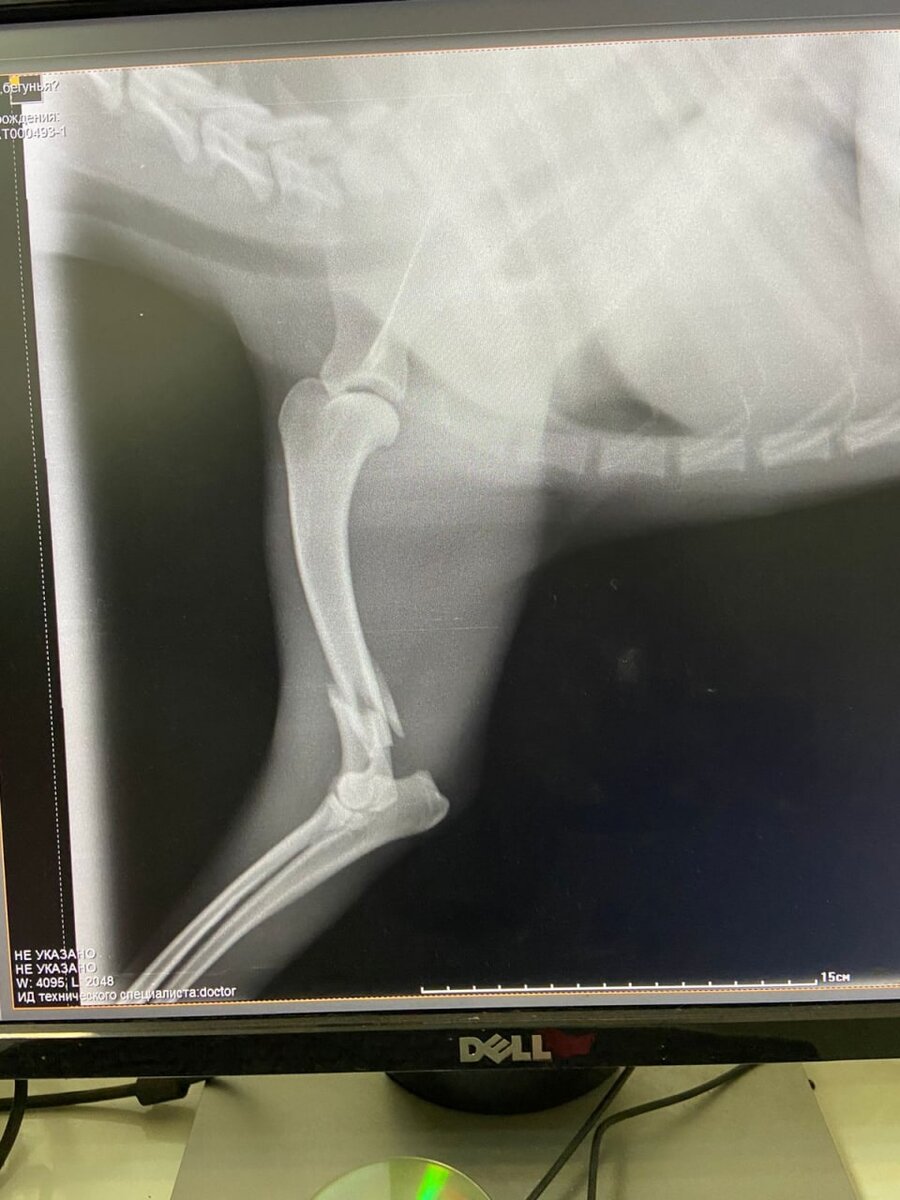

Через пару часов молоденькую Рыжулю уже обследовали в приюте. Подтвердились наши опасения, на снимке был перелом лапки

Наши доктора провели операцию. Затем целый месяц пребывания в клетке для иммобилизации сустава.